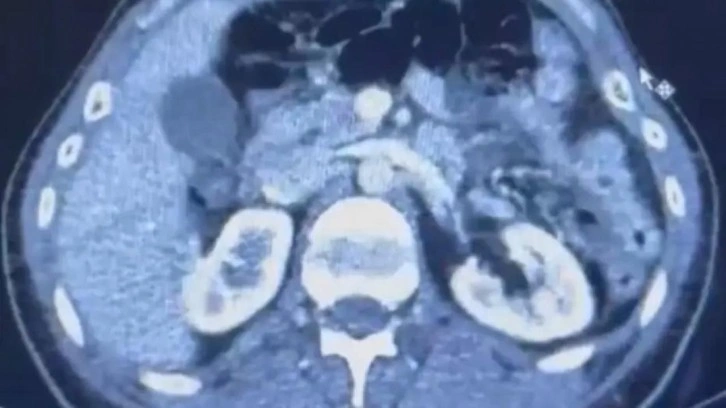

RÖNTGEN ÇEKİLDİ, KAPSÜLLER ORTAYA ÇIKTI

Şüphelilerden S.C. ve R.B.C. muayene edilmek üzere Kayseri Şehir Hastanesi'ne getirildi.

Röntgeni ve ultrason çekilen şüphelilerin midesinde yaklaşık 50 kapsülde 554 gram uyuşturucu olduğu tespit edildi.